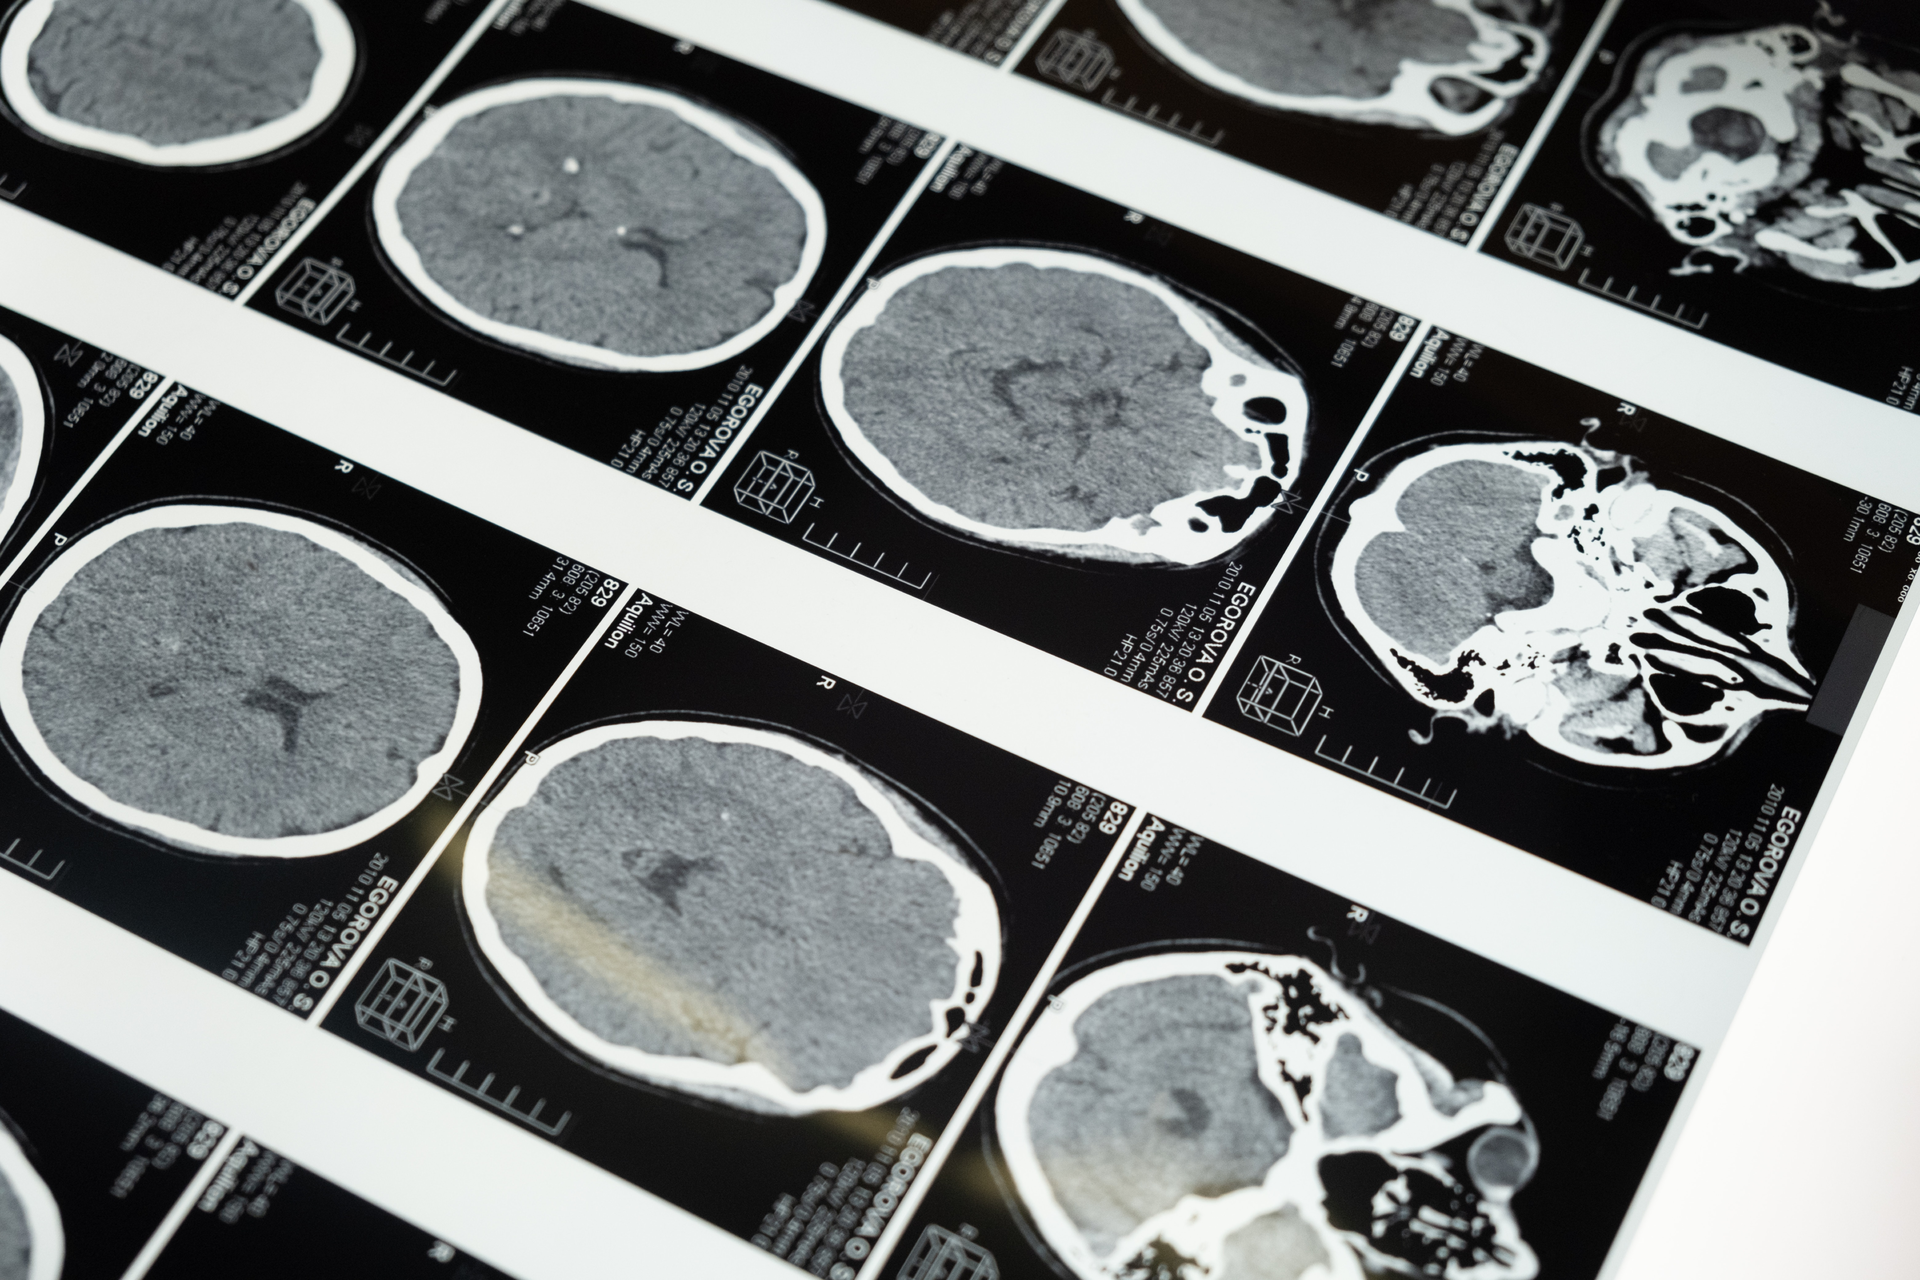

A stroke happens when blood supply to the brain is interrupted or reduced, preventing brain tissue from getting oxygen and nutrients. This causes brain cells to become damaged or die.